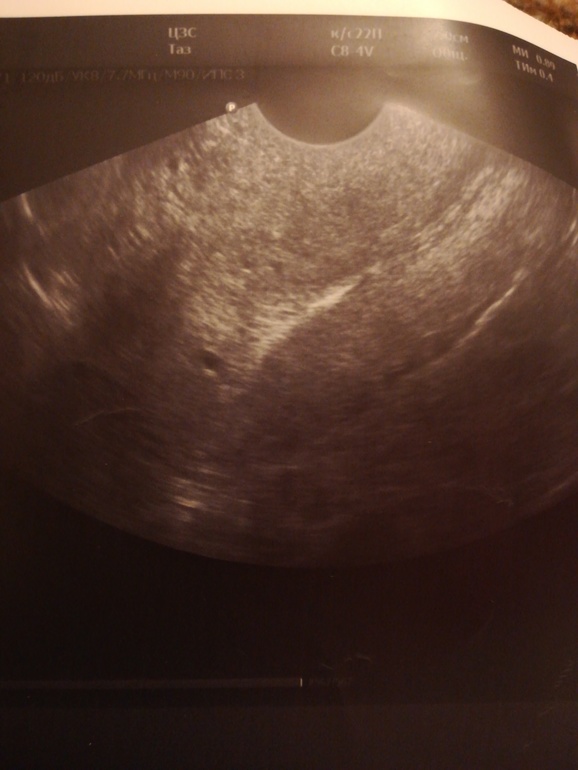

Плодное яйцо 0.4 см при хгч 50???😩

На узи 9 декабря врач не увидел признаков Б вообще.. Сказал что эндометрий 10мм, желтого тела нет ни в одном из яичников. Я с сожалением, что это Б*б и она сорвалась, стала ждать М. Но намёка на них нет вообще.. Грудь кстати совсем не болит, мягкая, не как в предыдущие 3 беременности.... Сегодня пошла на Узи, чтобы исключить ВБ, потому что хгч медленно, но рос все же.. Врач, уже другой, (не тот, который делал узи 9 декабря) , диагностировал Б, в полости матки ПЯ 0.4 см, жёлтое тело 18мм, эндометрий пышный 16мм. Назначила утрожестан, для поддержания... прогик был 10, очень низкий.Но врач была очень удивлена, что 10 декабря хгч 50, при таких низких цифрах ПЯ не видно было бы.. Может быть ошибка лабы или мог за 3 дня с 10.12. до 13.12. ХГЧ так скакануть? Тесты положительные, но полоски ещё не сравнялись даже . Несколько дней они были одного цвета, не ярчали совсем. Сегодня тест ярче, чем в предыдущие дни. Динамику наблюдала только по эвитест..

Доброй ночи всем. История продолжается. Хгч перестала сдавать на 6-ти с лишним тысячах..уж очень это нервное занятие)) .. С 22 по 26 декабря вырос с 2000 до 6248. Сейчас у меня другая загадка, до 20 декабря видели одно ПЯ на узи. 26 декабря увидели 2пя рядом.. Маленькие очень. 5,3 и 4,3 мм. 30 декабря узи - пя выросли до 7,4 мм и 6.1. Врач пока наблюдает, надеемся, что в пя появятся эмбрионы.. Говорит, с близнецами и двойнями видела всякое. Иногда они медленнее растут. Хотя, конечно, я очень боюсь замершей и анэмбрионии.. Но надеюсь из последних сил на лучшее и на чудо 🙏. На узи теперь пойду после праздников, дабы не портить себе нервы этими раздумьями. Думаю, что последнее узи все прояснит. На фото ниже динамика пя 26 и 30 декабря. И ещё большой вопрос, как одно пя сначала было 4мм, потом 9мм и превратилось в два? Врач сказал, двойню не всегда сразу видно.. Она выявляется ближе к 6-7 нед.

Плодное яйцо можно увидеть при хгч не менее 600-800 а как правило 1000.

Либо ошибка лабы, либо сегодня ничего не увидели. У вас есть снимок ПЯ.

Очень похоже на то узи что я ниже показала.

У вас два варианта либо лаба ошиблась и хгч ц вас как минимум 500 ( с 50 до 500 за 2 дня он не мог скакануть)

Либо у вас это не ПЯ, а миома как у моей подруги

Хгч странный конечно, а размер плодного яйца норм. У меня на 18 дпо было 4 мм

Да, вот узи сегодня и фото